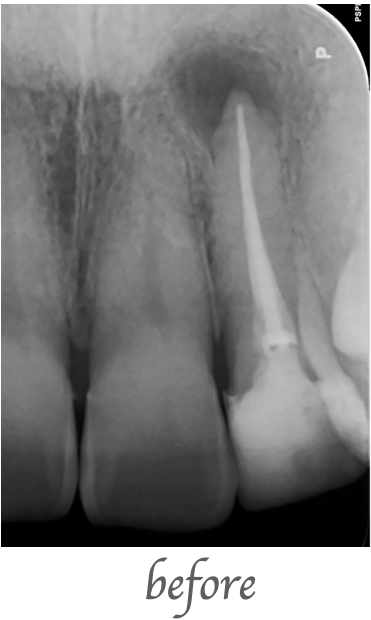

レントゲンで左上の前歯の根の先に大きな病巣が見つかったため、精密根管治療を行いました。ラバーダムを行い、歯科用顕微鏡(マイクロスコープ)、ニッケルチタンファイル、MTAセメントを使用し根管充填を行いました。

治療期間:約2週間 治療回数:2回

¥70,000(税込77,000)

治療直後に軽微な痛みが出ることがあります。根尖病巣の再発、症状改善が認められない場合があります。